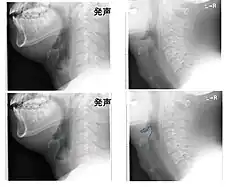

Left column: Normal epiglottis. Right column: Epiglottitis.

On lateral C-spine X-ray, the thumbprint sign describes a swollen, enlarged epiglottis.[11] A normal X-ray, however does not exclude the diagnosis.[11] An ultrasound may be helpful if specific changes are present, but its use as of 2018 is in the early stages of study.[11]